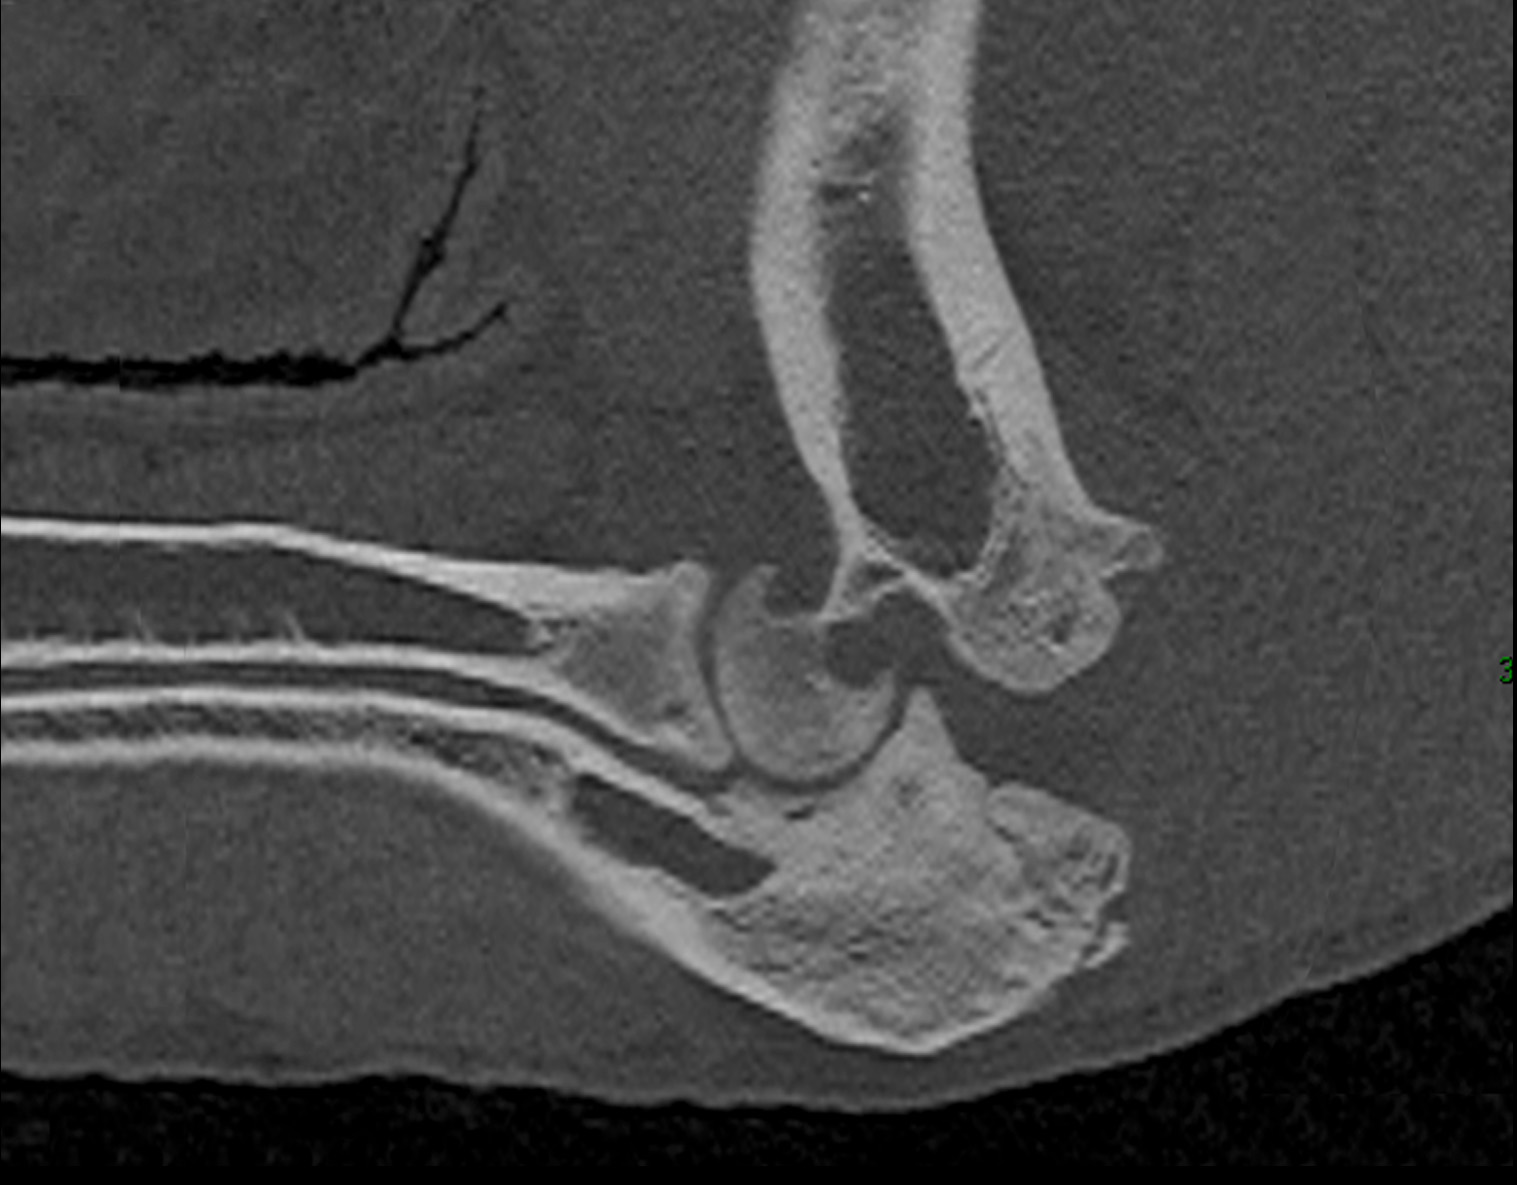

Breed: Kunekune Pig

Dates of Surgery: April 24, 2022

Product: TATE Elbow®

“Willow was examined at Cornell after being rescued and taken into the care of Where Pigs Fly Rescue & Sanctuary. She had chronic, multi limb lameness that required an intensive pain control regime to facilitate basic day-to-day movement, such as standing for meals. Although hind-limb surgery to treat a luxating patella improved her gait, Willow had difficulty rising and ambulating due to crippling left elbow arthritis. A Total Elbow Replacement (TER) was elected to treat discomfort and preserve joint function to the greatest extent possible. Since her surgery, Willow has physiotherapy exercise and an intensive medication program. She has gradually been weaned from her pain medication and is now able to enjoy outside time, savor her favorite snacks, and move around the pasture at her new home, Arthur’s Acres Animal Sanctuary!”